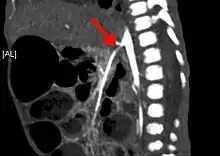

| CT angiogram demonstrating stenosis of the superior mesenteric artery. | |

Abdominal angina is diagnosed by identifying stenosis with imaging.[10] Since the symptoms of abdominal angina overlap with various other disorders, other causes of symptoms are ruled out as a part of the diagnostic process. Gastric ulcers, abdominal aortic aneurysms, and gastrointestinal cancers can have similar symptoms and can be ruled out by esophagogastroduodenoscopy, CT scans, or MR angiogram. Other differential diagnoses include GERD, dietary or food sensitivities, constipation, pancreatitis, abdominal abscess, appendicitis, irritable bowel syndrome, gastroenteritis, hepatitis, and inflammation of the gastrointestinal system.[11] Duplex ultrasound, MR angiography, angiography, and computed tomography angiography can be used to help confirm the diagnosis of abdominal angina.[3] Duplex ultrasound may be used to screen for abdominal angina but is not ideal for visualizing stenosis. Angiography, MR angiography, or CT angiography can be used to further visualize the celiac and mesenteric arteries.[12]